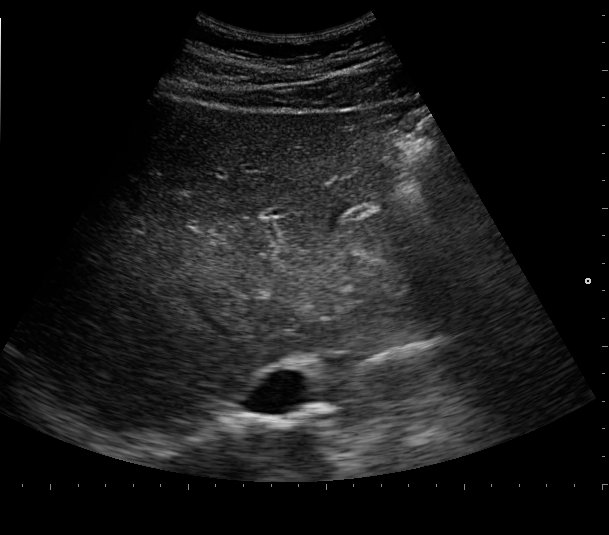

Evaluation:

-clinic and lab work up including hemostasis parameters

-ultrasound!!!👉abnormal portal vein waveform, marked thickening of the gallbladder wall, and a hepatic artery resistance index >0.75

-liver biopsy (transjugular)